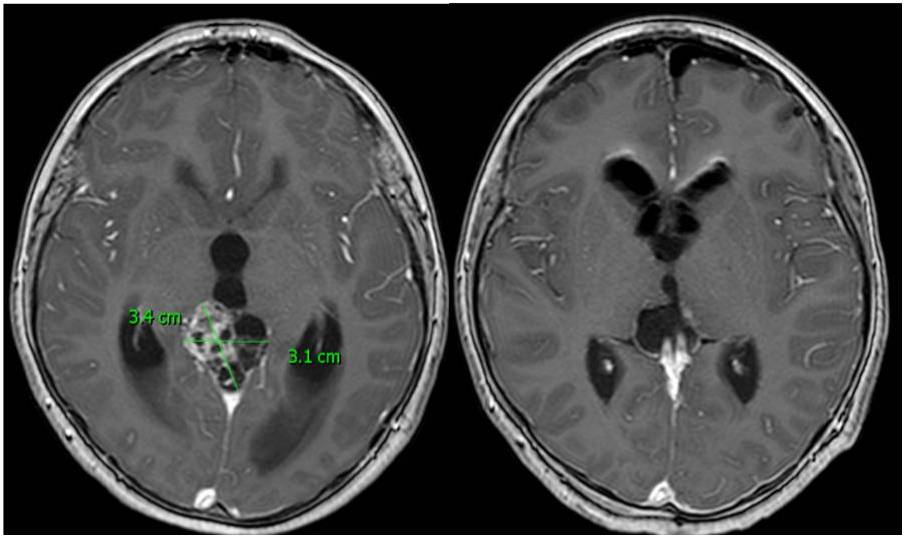

Glioblastom na magnetické rezonanci Metastáza na magnetické rezonanci

Glioblastom před operací, (horní řádek), bezprostředně po radikální operaci (střední řádek) a po půlročním sledování (dolní řádek).